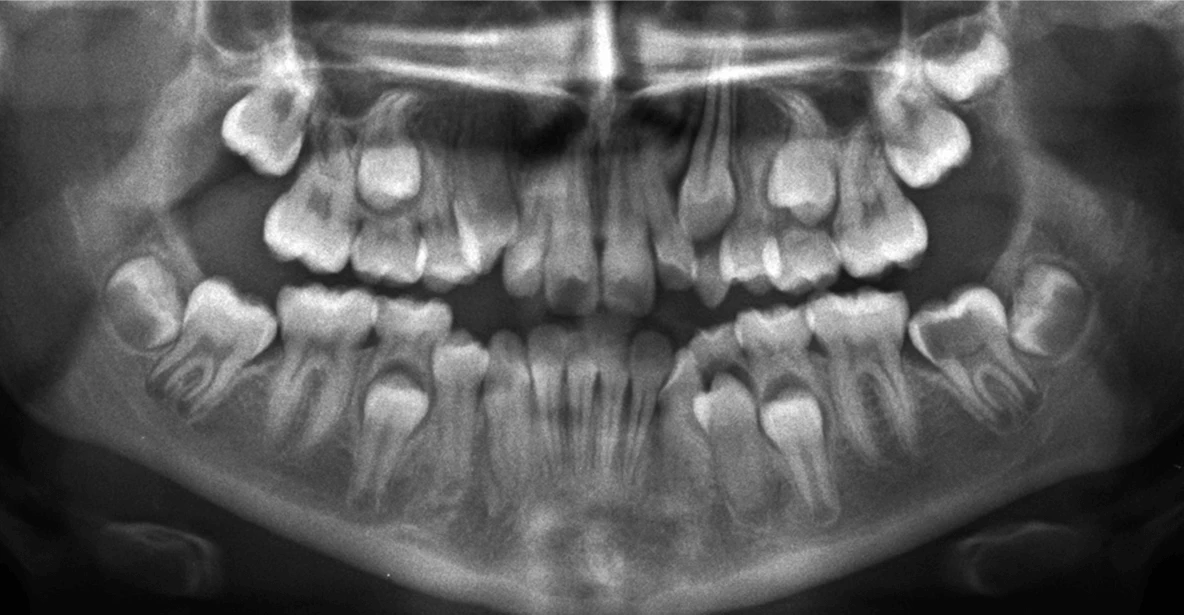

- Solicitaremos una radiografía panorámica para analizar su desarrollo dental.

- Si ya cuentan con una radiografía actualizada, pueden traerla directamente a la consulta.

Radiografía panorámica de dientes sin erupcionar